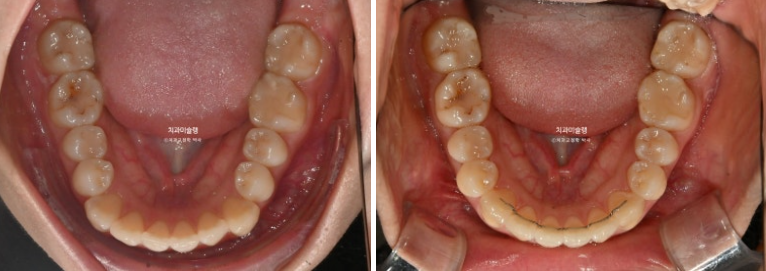

25.03~25.12

이 사진에서 보듯 치아가 초진에 비해 작아질 정도까지 치간삭제를 하지는 않습니다.

만약 치아가 작아보일 정도까지 했거나 치아가 시려질때 까지 했다면 그건 치간삭제를 너무 과하게 한거죠.

통상 에나멜층에 한정해서 부위당 0.2mm씩 최소량 시행하면 치료에 도움이 됩니다.

그러나 그 양이 과하면 치아건강을 해지게 되겠죠.

과유불급 이라는 말처럼요.